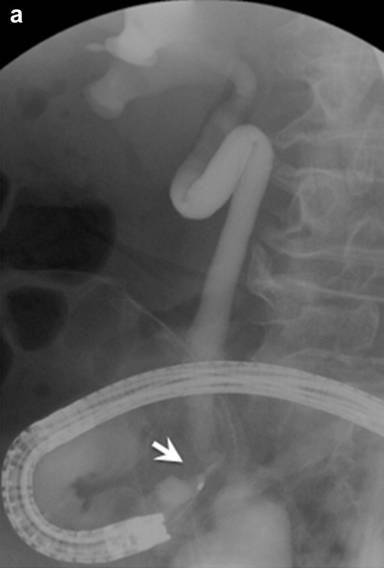

Six months after starting steroid treatment, a right hydronephrosis appeared on the CT image. This urinary dilation disappeared two months later; however, bilateral hydronephrosis re-emerged in another two months. The dilation included the entire ureter, from the ileal junction to the renal pelvis, without ureteral stones. In the subsequent treatment course, the patient suddenly developed septic shock. Because of the existing hydronephrotic findings, urinary infection was suspected. The causative bacterium detected in the blood was Proteus mirabilis, which was also positive in the urine culture, and a suitable antibiotic was administered. Retrograde ureteropyelography using duodenoscope showed a severe stricture at the upper portion of ureteroileal junction, 8 mm in length (Figure 2a). A double-J stent (7F) was inserted and a similar attack never reoccurred, although the spontaneous remission and recurrence of the bilateral hydronephrosis was repeated.

Figure 2. Images of systemic lesions after starting steroid therapy. a. Endoscopic retrograde ureterography showed a stricture at the lower portion of right ureter, 8 mm in length (arrow). b. Following computed tomography demonstrated a large stone (7x10 mm) stuck in the main pancreatic duct at pancreatic head (arrow) and many small stones distributed within the pancreatic body and tail. c. Following endoscopic retrograde pancreatography demonstrated a stone stuck in the dilated main pancreatic duct at pancreatic head (arrow) and floating stones in the upstream (small arrows). |

In autoimmune pancreatitis, various extrapancreatic lesions occur in correlation with the disease activity [7], especially in cases with high serum IgG4 [16]. However, at present, the association with autoimmune condition has not yet been clarified in many systemic lesions [3]. In the present case, an association of the stenosis at the ureteroileal junction (Figure 2a) was not determined for the autoimmune condition. In general, postoperative urinary dilation or anastomotic stricture develops with a frequency ranging from 3% [17] to 10% [18] after cystectomy. Retroperitoneal fibrosis, a causative lesion of hydronephrosis in cases of autoimmune pancreatitis, was also not evident in our case. Hence, simple coincidence cannot be discounted; however, we rather suspect an association of the urinary stricture with autoimmunity because of its spontaneous remission and recurrence in bilateral ureters.